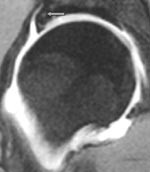

Tabell 1 viser våre funn. Labrum ble tydelig fremstilt på alle MR-artrogrammene. Normal labrum er triangulær i tverrsnitt og med lavt signal. Den er tynnere anteroinferiort og tykkere posterosuperiort. Nedad går den sammen med ligamentum transversum. Den perilabrale recess sees normalt superiort hvor leddkapselen hefter seg noen millimeter over øvre del av labrum (fig 2). Denne recess er mye mindre anteriort og posteriort.

Degenerativ labrum viste økt signalintensitet i labrum uten affeksjon av overflaten med inntakt recess hos to pasienter (fig 3) og med manglende fremstilling av recess hos tre pasienter (fig 4). Sistnevnte ansees forårsaket av labrumhypertrofi. Labrumruptur ble diagnosisert hos ti pasienter. Ruptur ble beskrevet når man kunne identifisere kontrast mellom labrum og acetabulum (fig 5) eller imbibering av kontrast i labrum (fig 6). Alle rupturene satt i øvre del av labrum.To av disse pasientene er operert, og vårt funn ble verifisert. Begge var aktive fotballspillere, og de hadde henholdvis stadium 2B og stadium 3B ved MR-artrografi. Dette samsvarte med de artroskopiske funn. Den tredje pasienten som er operert, viste forandringer forenlig med villonodulær synovitt. Også dette ble verifisert ved artroskopi (fig 7).

Normal labrum er trekantet og lavsignalgivende ved MR-artrografiseriene, bortsett fra tilheftingen av labrum til acetabulærbrusken, hvor det er et lite, fokalt område med høyere signalintensitet. Dette representerer sannsynligvis degenerativt bindevev her. Ved konvensjonell MR kan man overdiagnostisere en ruptur (7), men ved MR-artrografi vil det ikke være noen imbibering av kontrast.